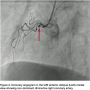

The patient was shifted immediately to the catheterization laboratory after informed consent was obtained for primary percutaneous intervention. Coronary angiography revealed that the left main coronary artery was normal and gave off the large left anterior descending (LAD) and left circumflex (LCX) arteries. The LCX was a non-dominant artery and free of disease. The LAD continued in the anterior interventricular groove with 100% occlusion after the septal branch (Figure 1). The right coronary artery was a nondominant, diminutive vessel arising from the right coronary sinus, ended in the right anterior atrioventricular groove, and was free of disease (Figure 2).